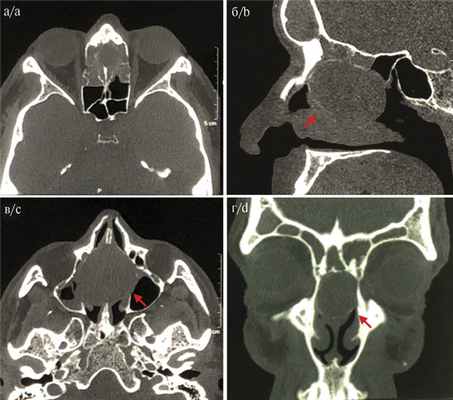

По данным компьютерной томографии (КТ) носа и ОНП с контрастированием (омнипак 50 мл), в верхних отделах перегородки носа было выявлено округлое образование с четкими ровными контурами, однородной структуры, плотностью 22—30 ед. Н, размером 40×35×29 мм, заполненное патологическим содержимым и распространяющееся в полость носа (рис. 3). Рис. 3. КТ ОНП пациента перед хирургическим вмешательством. а — аксиальная проекция; б — коронарная проекция; в — аксиальная проекция; г — сагиттальная проекция. Во всех проекциях стрелками указано мукоцеле. Был выставлен предварительный диагноз: мукоцеле перегородки носа.